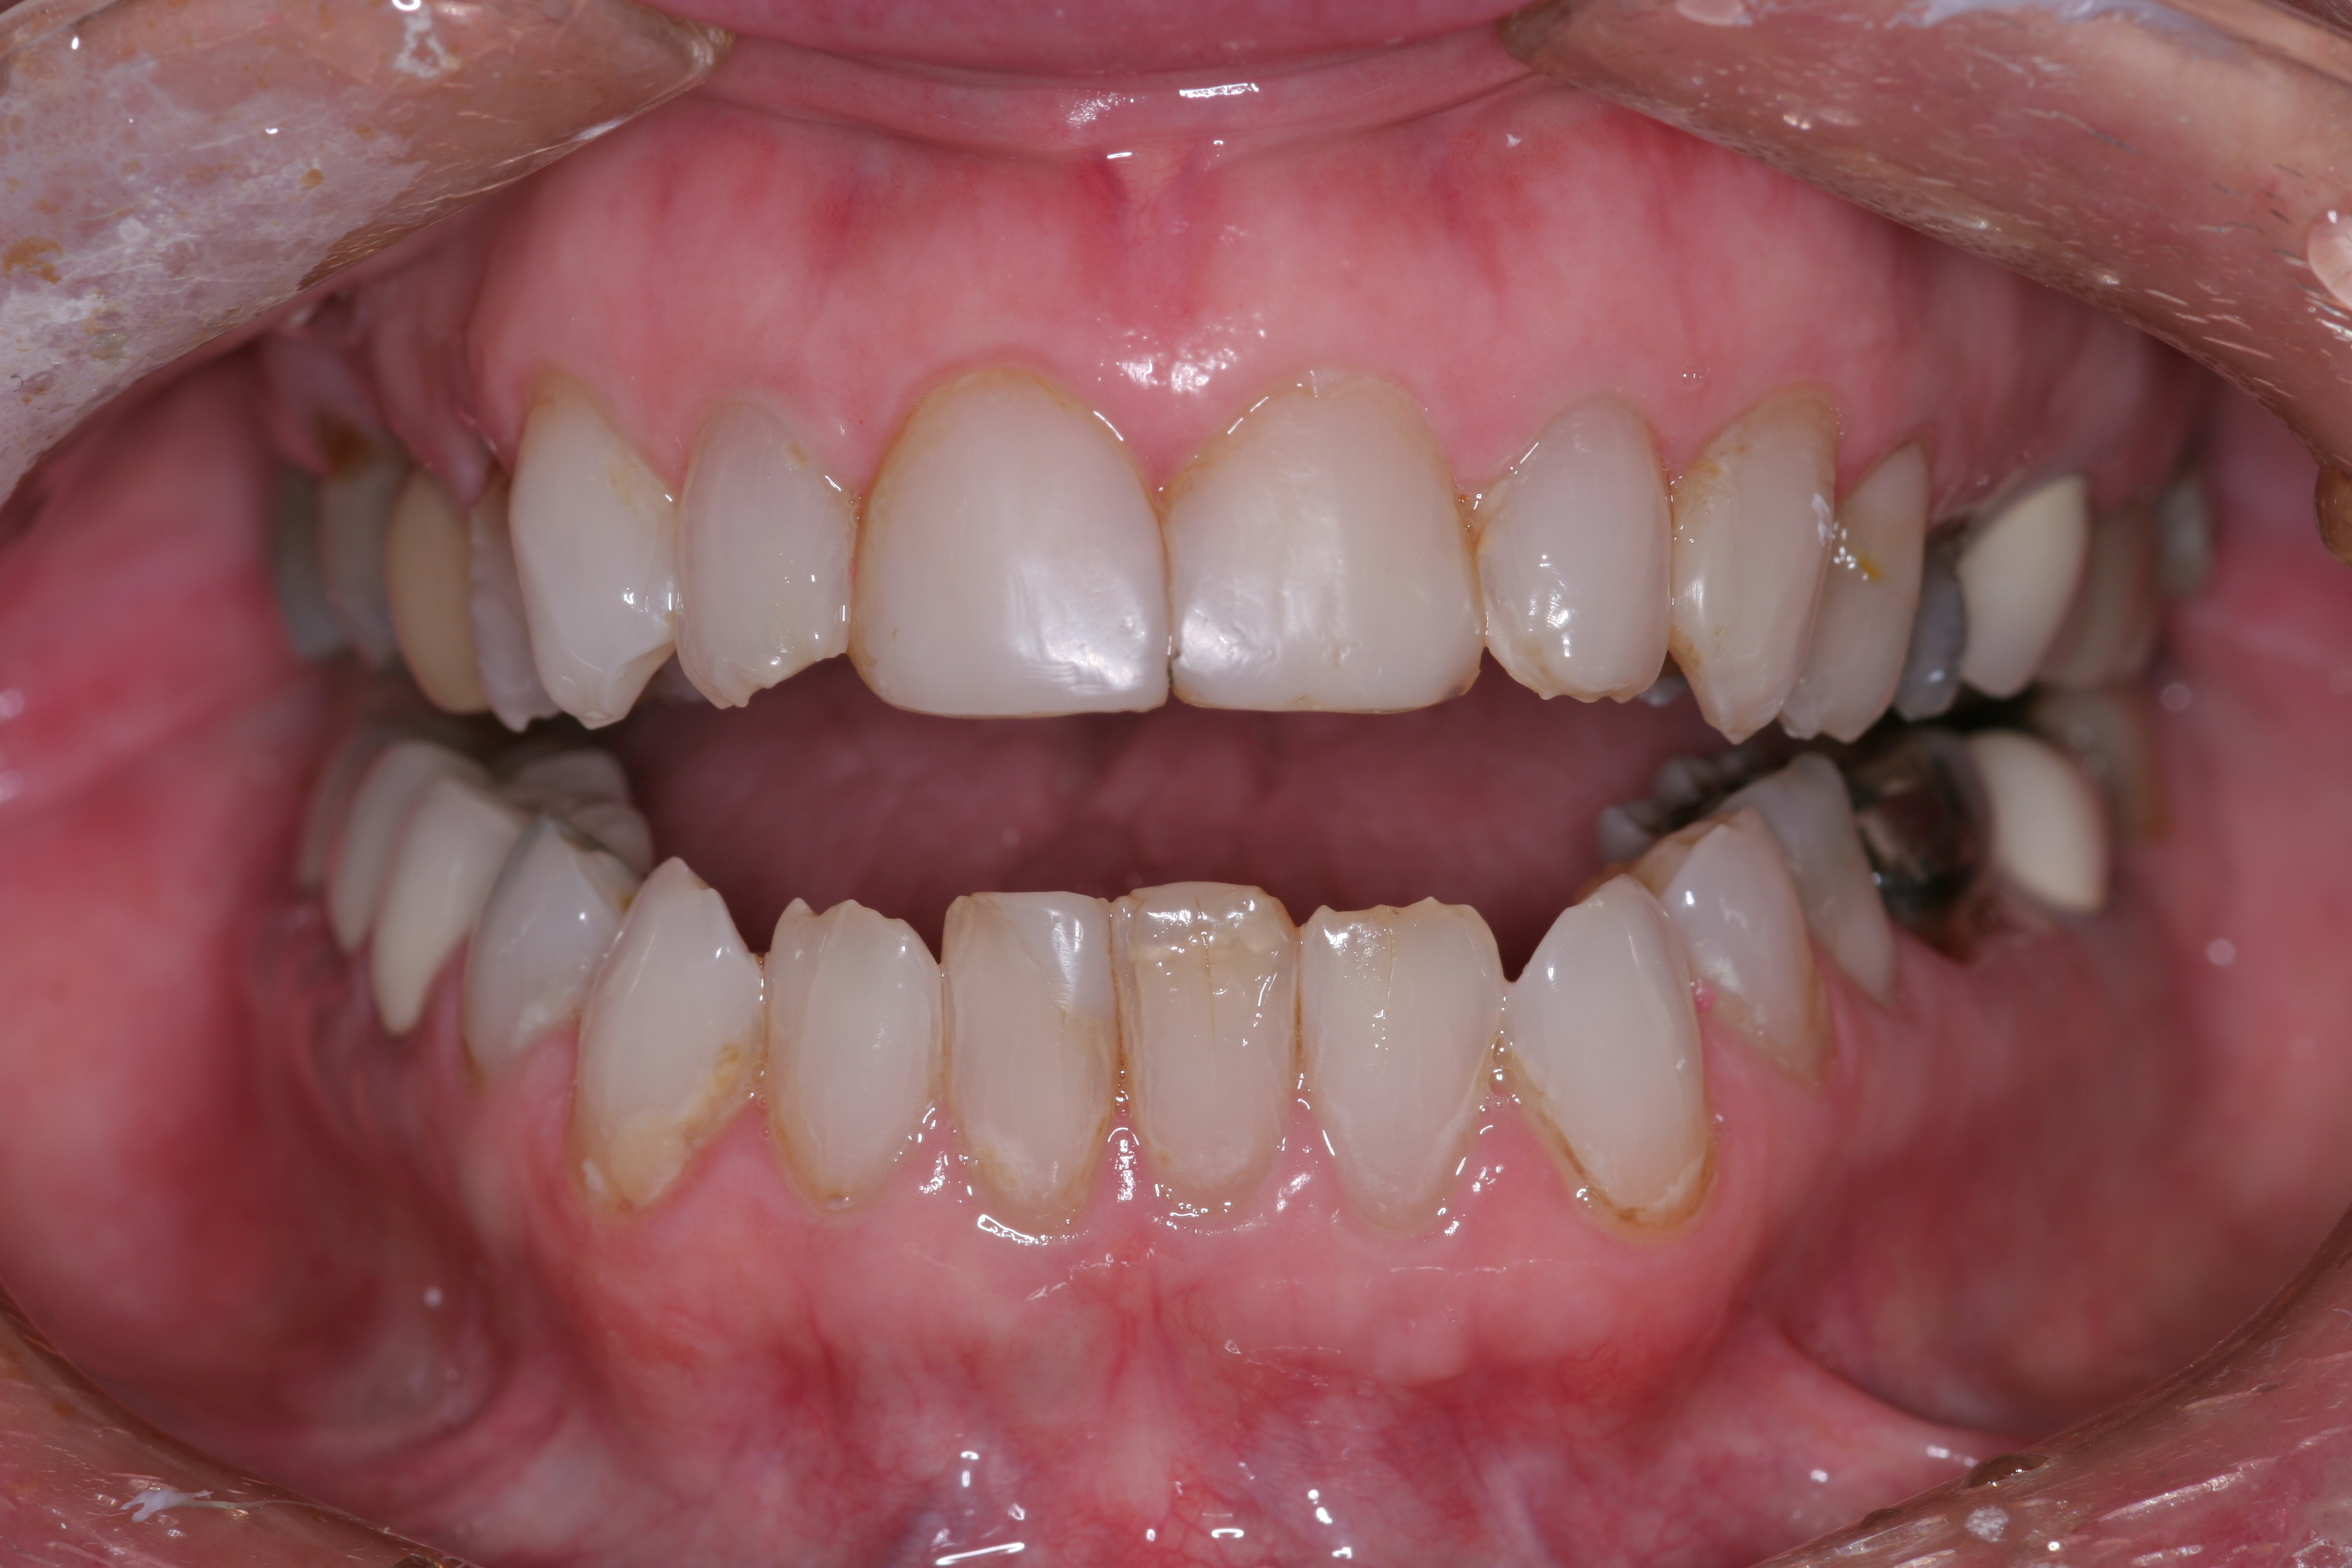

(10.) A patient presented with advanced generalized wear of her anterior teeth, and was displeased with their overall appearance because of their color and wear.

Figure 10

(11.) A patient presented with advanced generalized wear of her anterior teeth, and was displeased with their overall appearance because of their color and wear.

Figure 11

(12.) A patient presented with advanced generalized wear of her anterior teeth, and was displeased with their overall appearance because of their color and wear.

Figure 12

A patient presented with advanced generalized wear of her anterior teeth (Figure 10 and Figure 11). She was displeased with their overall appearance because of their color and wear (Figure 12). A complete examination was performed, revealing instability in her temporomandibular lateral poles bilaterally, sore muscles of mastication, advanced wear, a CR/MIP discrepancy, and loss of her anterior guidance due to the wear. Although the topic is beyond the scope of this article, the patient was also screened for possible sleep apnea. This included an evaluation of the Mallampati score, previous sleep therapy evaluation or treatment, snoring history, an evaluation of her neck size, her weight status, and the presence of the tonsils and their size. In every case, if this clinician suspects airway obstruction to be playing a role in tooth wear issues, the patient is referred to a sleep physician. The patient in this case displayed few apnea risk factors, and the patient’s anterior wear facets fit together like a “lock and key” pattern seen in parafunctional activity. Splint therapy was initiated to stabilize the joints and muscles. A repeatable CR position was verified through load testing. At this point diagnostic models, photographs, a CR bite record, and a facebow were taken and recorded.